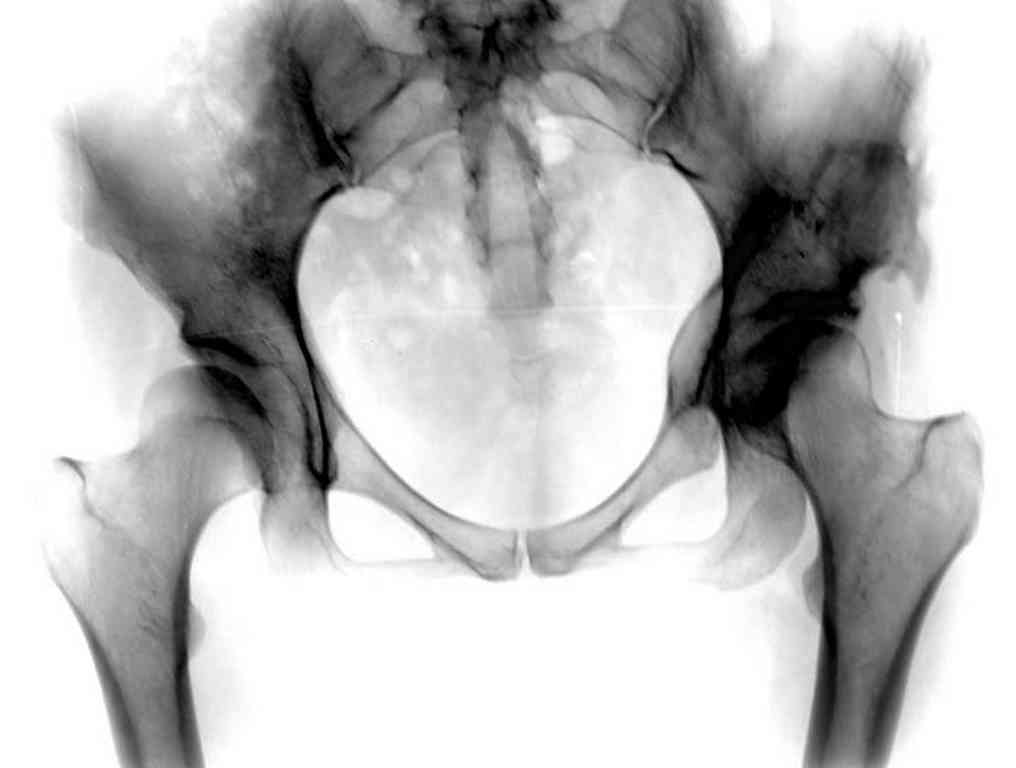

Представляю Р-снимки: обзорная, с отведением и с приведением.

Глубокоуважаемый Абдурашид. Здесь нет снимка с отведением. Если Вы сами сходили в рентгенкабинет и лично отвели пораженную конечность максимально возможно, а также дали максимально возможную внутреннюю ротацию-это одно!!!! Значит у пациентки тяжелейшая приводящая контрактура тазобедренного сустава!! И необходимо разобраться-миогенная или артрогенная? Если же Вы просто назначили указанный снимок и доверили произвести укладку рентгентехнику-это другое!!! Одному богу известно, что она делала, ведь на р-снимке отведения нет!

Все предыдущие корреспонденты предлагают вам достаточно простую вещь-смоделировать предлагаемую Вами операцию (т.е. дать отведение и внутреннюю ротацию) и посмотреть, как изменятся соотношения в суставе. Не обижайтесь, но судя по представлению клинического случая угловые величины, характеризующие пространственные соотношения в тазобедренном суставе, ваши рентгенологи не считают.

Данный сустав в начальной стадии разрушения, но все-таки я бы сделал обзорный таз и отдельные снимки сустава в 30 градусной абдукции и аддукции. Также снимки с внутренней и наружной ротацией для оценки состояния головки бедра.

Глубокоуважаемый Игорь Владимирович! Признаюсь допустил ошибку, из-за напряженности работы и нехватки времени, когда повторно внимательно посмотрел все понял и не успел исправить ошибку до Вашего поста, конечно скошенность крыши в пределах 40гр,часть головки кнаружи линии Омбредана-Перкинса , облитерация дна вертлужной впадины и т.д.-это ДМВБ.